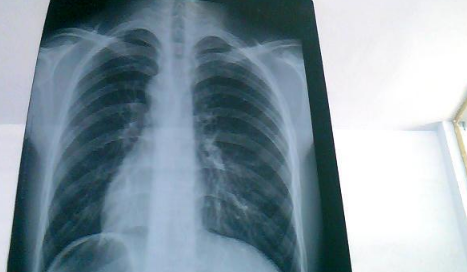

白肺是目前很常见的情况,受新冠影响很多老年人都出现了白肺的情况,当然也有年轻人会患上白肺。那么,如何自查是否出现白肺?平时怎样保护自己的肺?一起来看看趣丁网带来的详细介绍吧!

如果出现白肺,患者可能会出现一些严重的呼吸道症状,包括咳嗽、喘息、呼吸困难或体力活动时呼吸短促。一个更客观的指标是病人的呼吸频率,通常大于每分钟30次呼吸,或血氧饱和度低于93%就要警惕出现严重肺部感染。白肺并不能预防,只能预警。

肺白了还能恢复吗

肺白了一般是指白肺,白肺能否恢复与疾病类型、严重程度有一定关系,有些患者在检查时,发现肺白密度增高,如果是轻度肺部炎症引起的白肺一般是可以恢复的,如果是严重肺部炎症或肺间质纤维化引起的,则可能无法恢复。